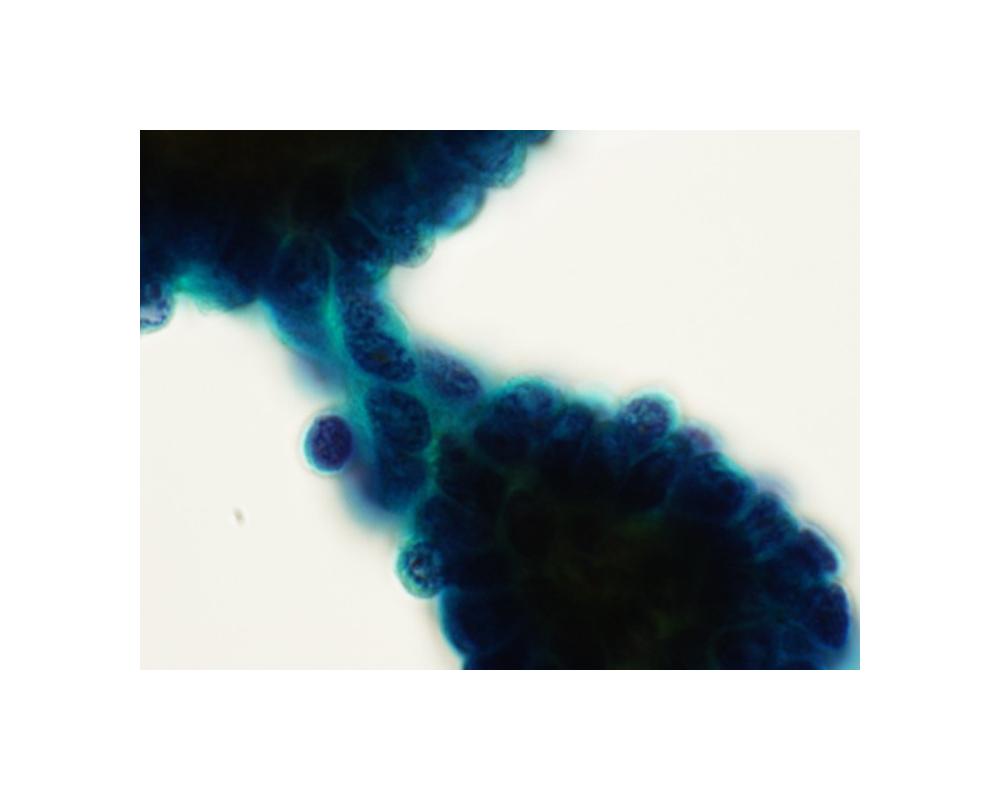

第38回日本臨床細胞学会九州連合会学会(熊本)スライドカンファレンス症例5

種別:体腔液

出題:和田 純平 大分県立病院臨床検査科病理部

| 年齢 | 50代 | 性別 | 女性 |

|---|---|---|---|

| 採取部位 | 胸水 | 採取方法 | 穿刺 |

| 検体処理法 |

臨床所見

既往歴:10年以上前に、腹部腫瘍の手術歴がある。

現病歴:X-10年に、胸水貯留の精査過程で腫瘍が認められ、現在まで化学療法を継続中である。直近の、胸水穿

刺吸引検体より作製された標本を提示する。

| 正解 | 5.高分化乳頭状中皮腫 |

|---|

▼選択肢及び投票結果

| 1.反応性中皮過形成 | 25件 | (24.0%) | |

| 2.腺癌 | 18件 | (17.3%) | |

| 3.扁平上皮癌 | 0件 | (0.0%) | |

| 4.上皮型悪性中皮腫 | 30件 | (28.8%) | |

| 5.高分化乳頭状中皮腫 | 31件 | (29.8%) | |

| 投票総数 | 104件 | (100%) |